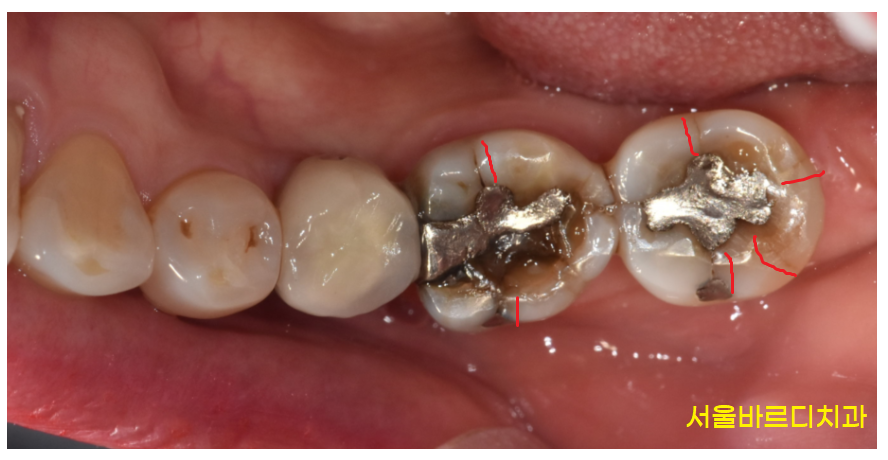

240622 예전 치료했던 치아 주변으로 금이 갔어요!

치아에 금이 가는 원인은 다양합니다.

한국 사람들은 딱딱하고 질긴 음식을 좋아하기에

미세한 금이 조금씩은 가있는데요.

특정 치아에 힘이 과도하게 가해질 경우

금에 심해질 수 있습니다.

또한 보철로 치료했던 부위에서 주변으로 금이 가기도 하죠~